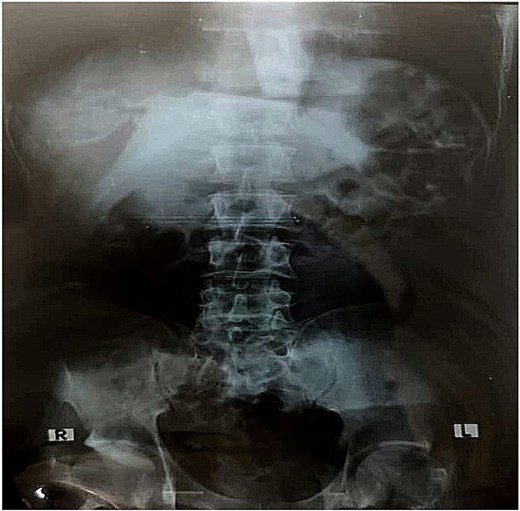

On current presentation, an abdominal X-ray (Fig. 1) showed no visible foreign body. Esophagogastroduodenoscopy (EGD) at a peripheral center (Fig. 2A and B) revealed a toothbrush lodged in the stomach with its head extending into the first part of the duodenum (D1); retrieval failed due to limited equipment.

Imaging findings can be inconsistent. While toothbrushes may appear as faint linear metallic densities on plain radiographs due to bristle staples [8], detection often fails on both X-ray and CT — as in our case — because of low radiodensity and artifact interference. This underscores the superiority of EGD for both diagnosis and removal.